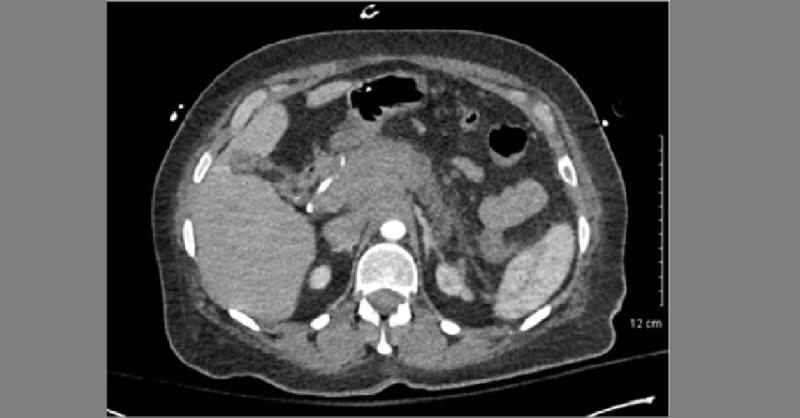

An elderly female presented to the emergency department with a chief complaint of “black tarry stools”. She had a past medical history of hypertension and noticed the “black tarry stools” two days prior to the presentation. Symptoms were not associated with abdominal pain, fatigue, weight loss, and other risk factors like smoking, alcohol intake, a